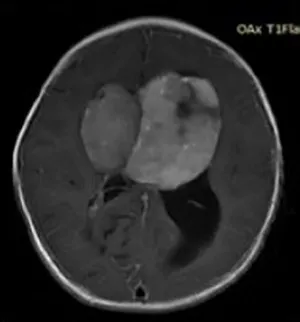

Couldwell教授演講中展示的部分巨大垂體瘤